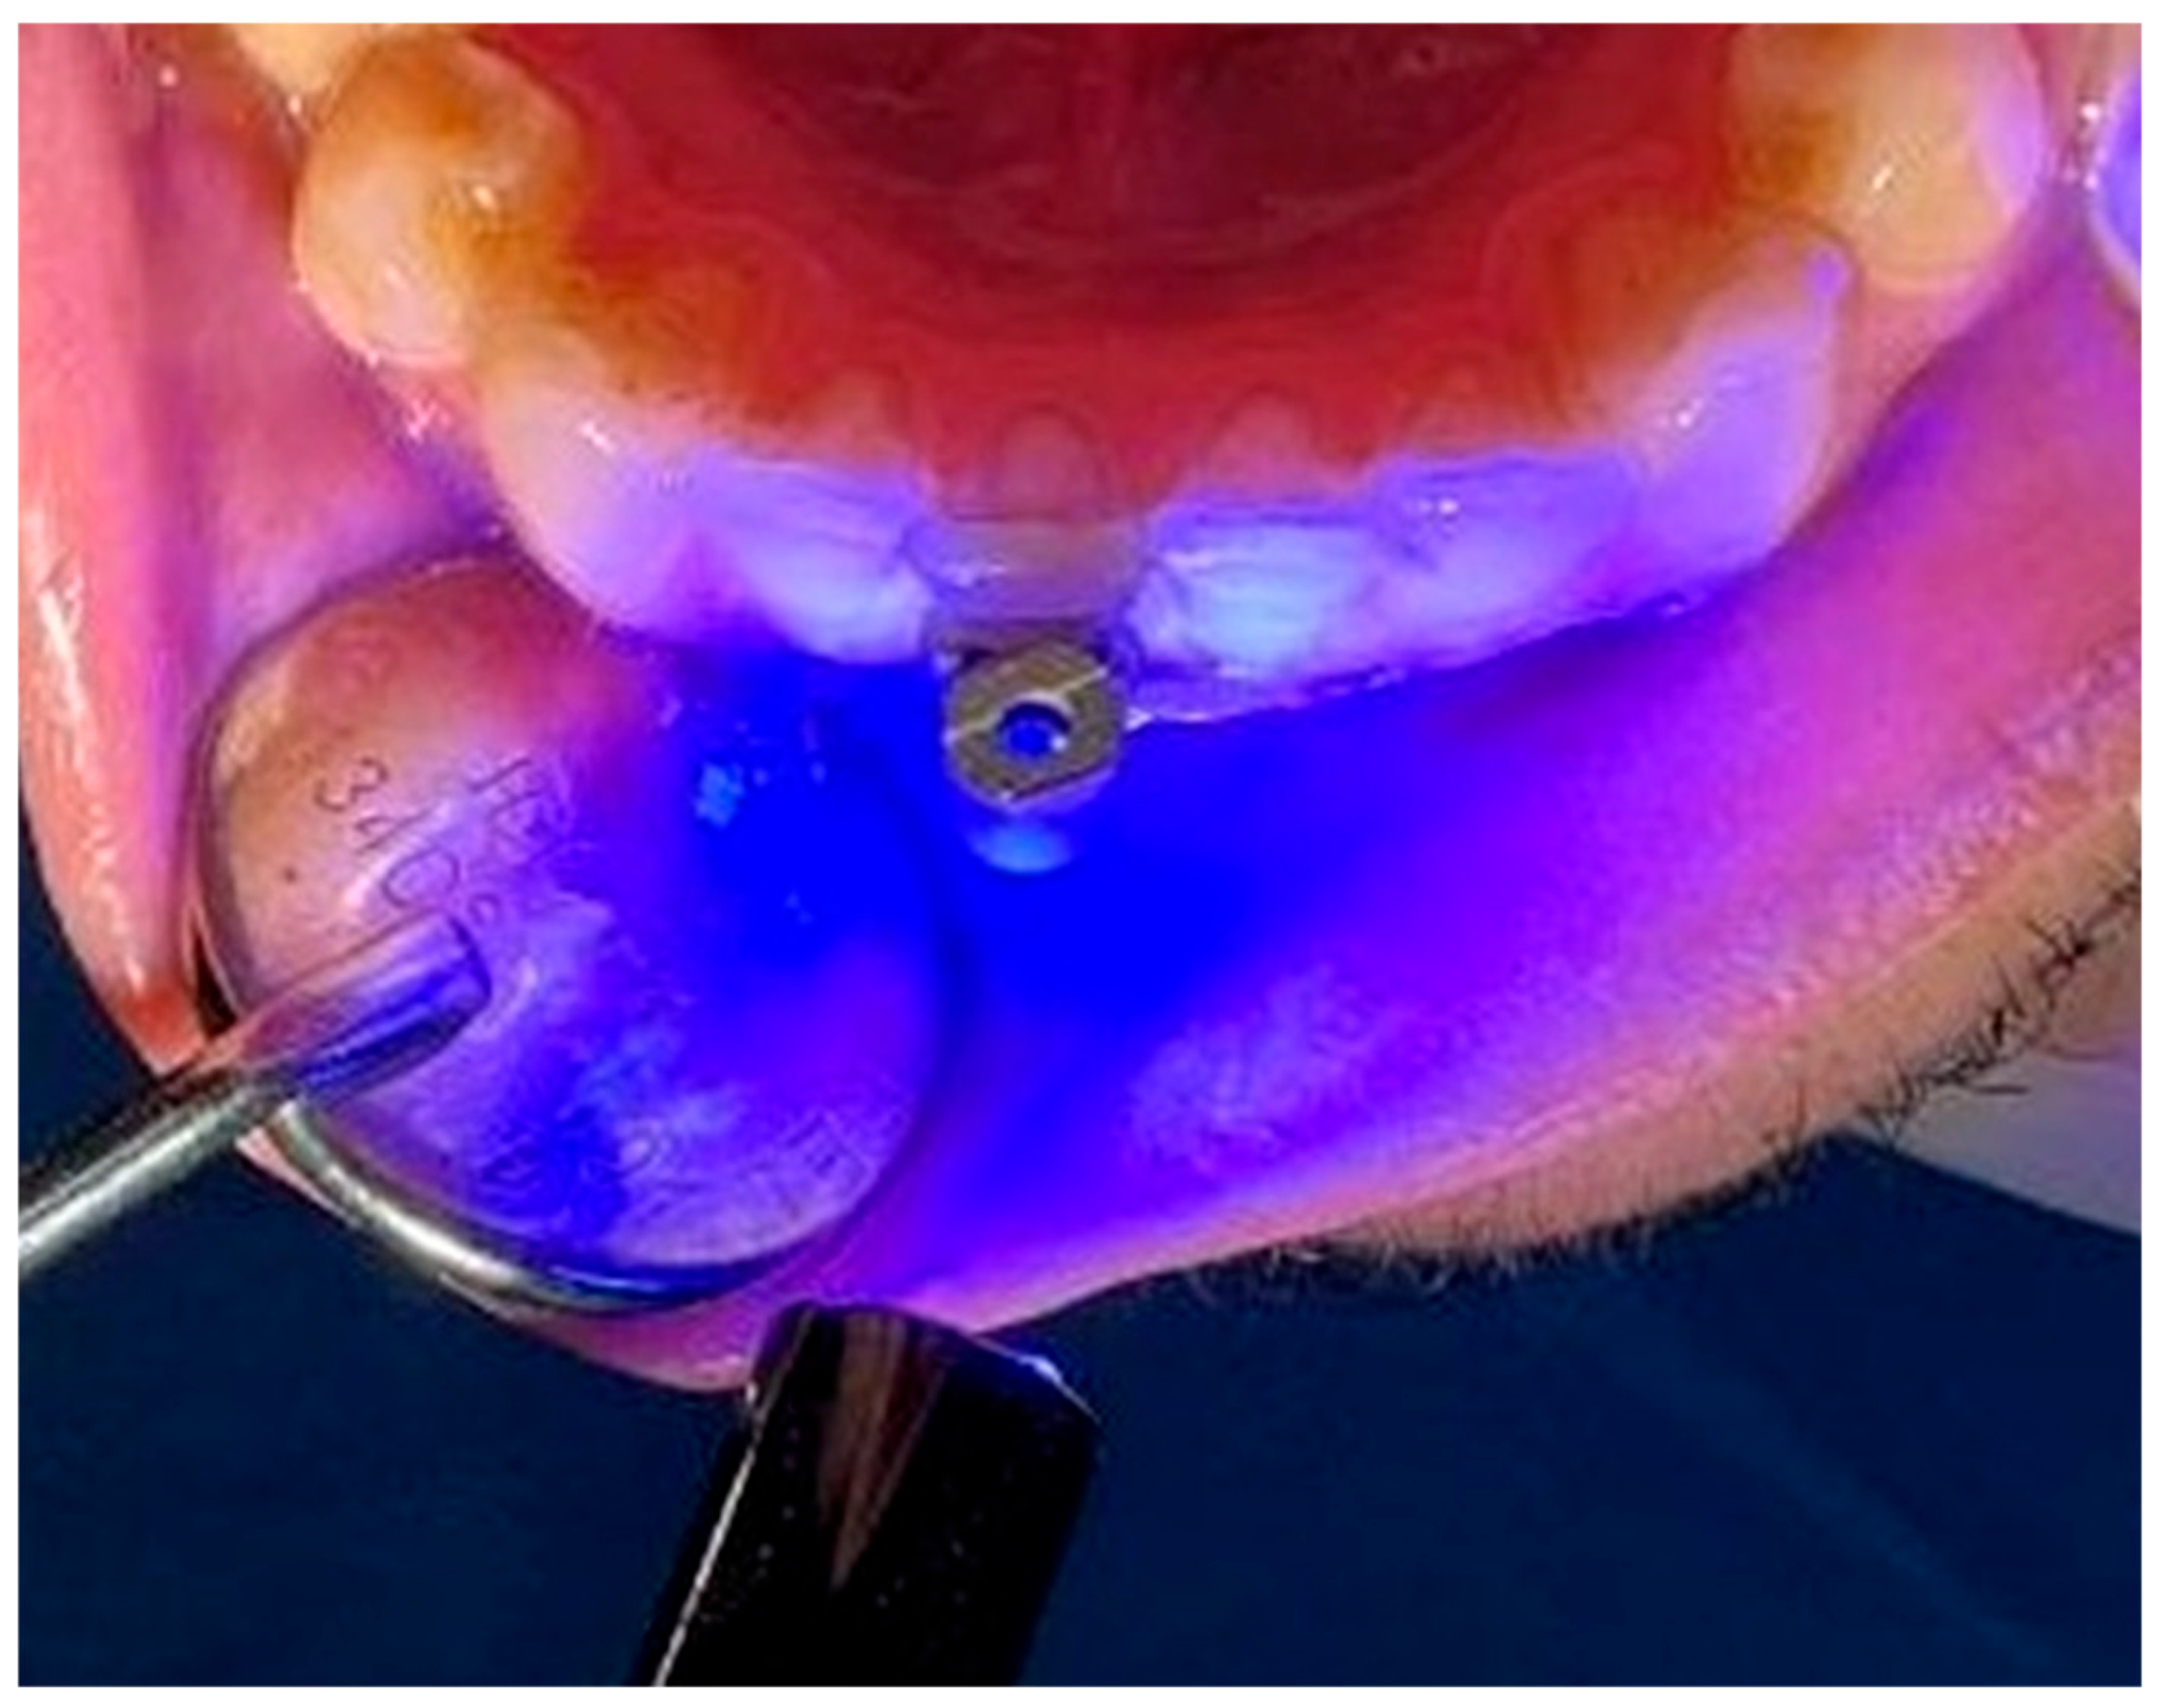

2. Materials and Methods

- Internally threaded to enable clockwise insertion of the modified SmartPeg (Figure 3b,c).

- Smooth texture with micro-mechanical retention properties (Figure 3a).